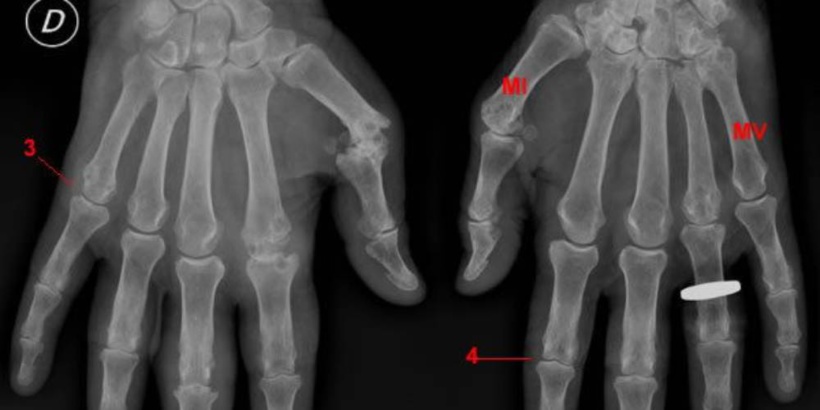

La polyarthrite rhumatoïde est la plus fréquente des diverses formes de rhumatismes inflammatoires chroniques regroupées sous l’appellation « arthrites chroniques ». Elle fait partie de ce que l’on appelle les maladies auto-immunes, maladies où l’immunité agresse le propre corps de la personne atteinte. C’est aussi une maladie de système n’atteignant pas toujours uniquement les articulations, mais aussi parfois d’autres zones du corps. Elle entraîne une inflammation de plusieurs articulations à la fois, qui gonflent, deviennent douloureuses et sont limitées dans leur amplitude de mouvement. Sans traitement, ces articulations ont tendance à se déformer progressivement au fil du temps. La polyarthrite rhumatoïde touche le plus souvent les mains, les poignets, les genoux et les petites articulations des pieds.

Un témoignage confirmé par le docteur Moustapha Niass du centre hospitalier universitaire Aristide le Dantec. Ce dernier convié à prendre part à cette manifestation, en a profité pour parler de la maladie et répondre aux questions des malades par des conseils. « Il s’agit d’une maladie auto-immune qui se produit lorsque le système immunitaire du corps commence à affecter son propre corps. La polyarthrite rhumatoïde peut également toucher d’autres parties que les articulations telles que la peau, les yeux, les poumons, le cœur et les vaisseaux sanguins. Les articulations les plus souvent touchées sont les mains, les pieds, les poignets, les coudes, les genoux et les chevilles» explique le médecin de l’hôpital Dantec qui a tenu à mettre en garde les malades sur le fait de ne plus prendre les médicaments prescrits. Ceci, pour se préserver des déformations articulaires.